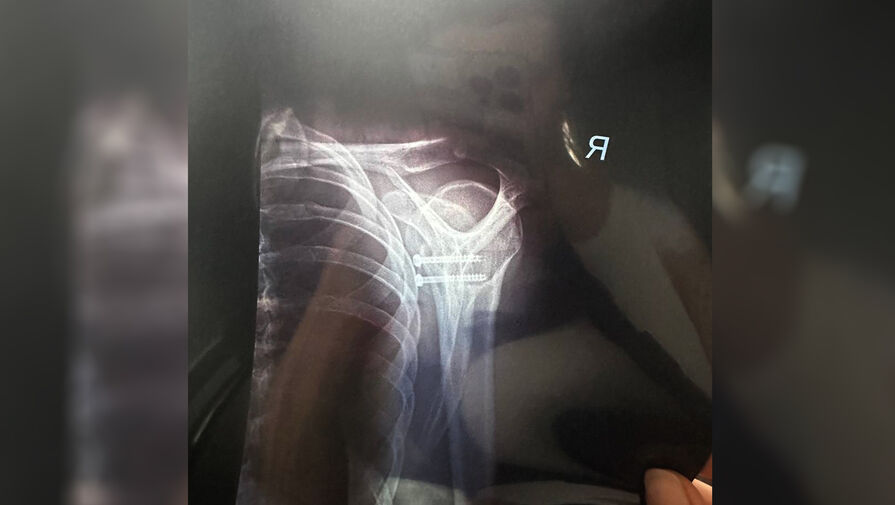

Олимпийская чемпионка по лыжным гонкам Наталья Терентьева (в девичестве Непряева) в своем Telegram-канале рассказала, что перенесла операцию, в ходе которой ей вставили в кость два винта.

«10 апреля — 31 мая. Наконец-то разобралась со старыми травмами, теперь мне ничего не помешает», – написала Терентьева.

Она отметила, что винты в ее кости установлены на пожизненный срок.